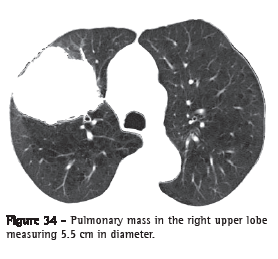

Mass (massa)

A mass is any expansive pulmonary, pleural, mediastinal or chest wall lesion presenting density of soft, fatty or bony tissue; greater than 3 cm in diameter; with at least partially defined contours; outside of the topography of the fissures and independent of the characteristics of its contours or the heterogeneity of its content (Figure 34).(7)